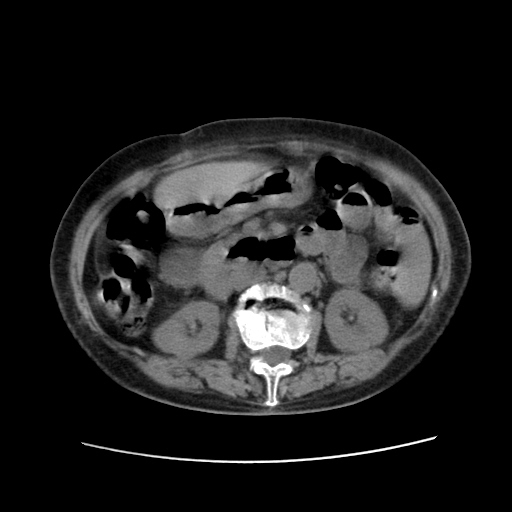

女,77.无不适

肝旁多发胆囊状液体影考虑肠腔积液基中部分囊状景不多外胆囊

肠子那块乱乱的没整明白

肝右叶肝内胆管结石并肝内胆管扩张。胆总管下段梗阻,考虑壶腹部占位。

肝右叶肝内胆管结石并肝内胆管扩张。胆总管下段梗阻,考虑壶腹部占位。支持